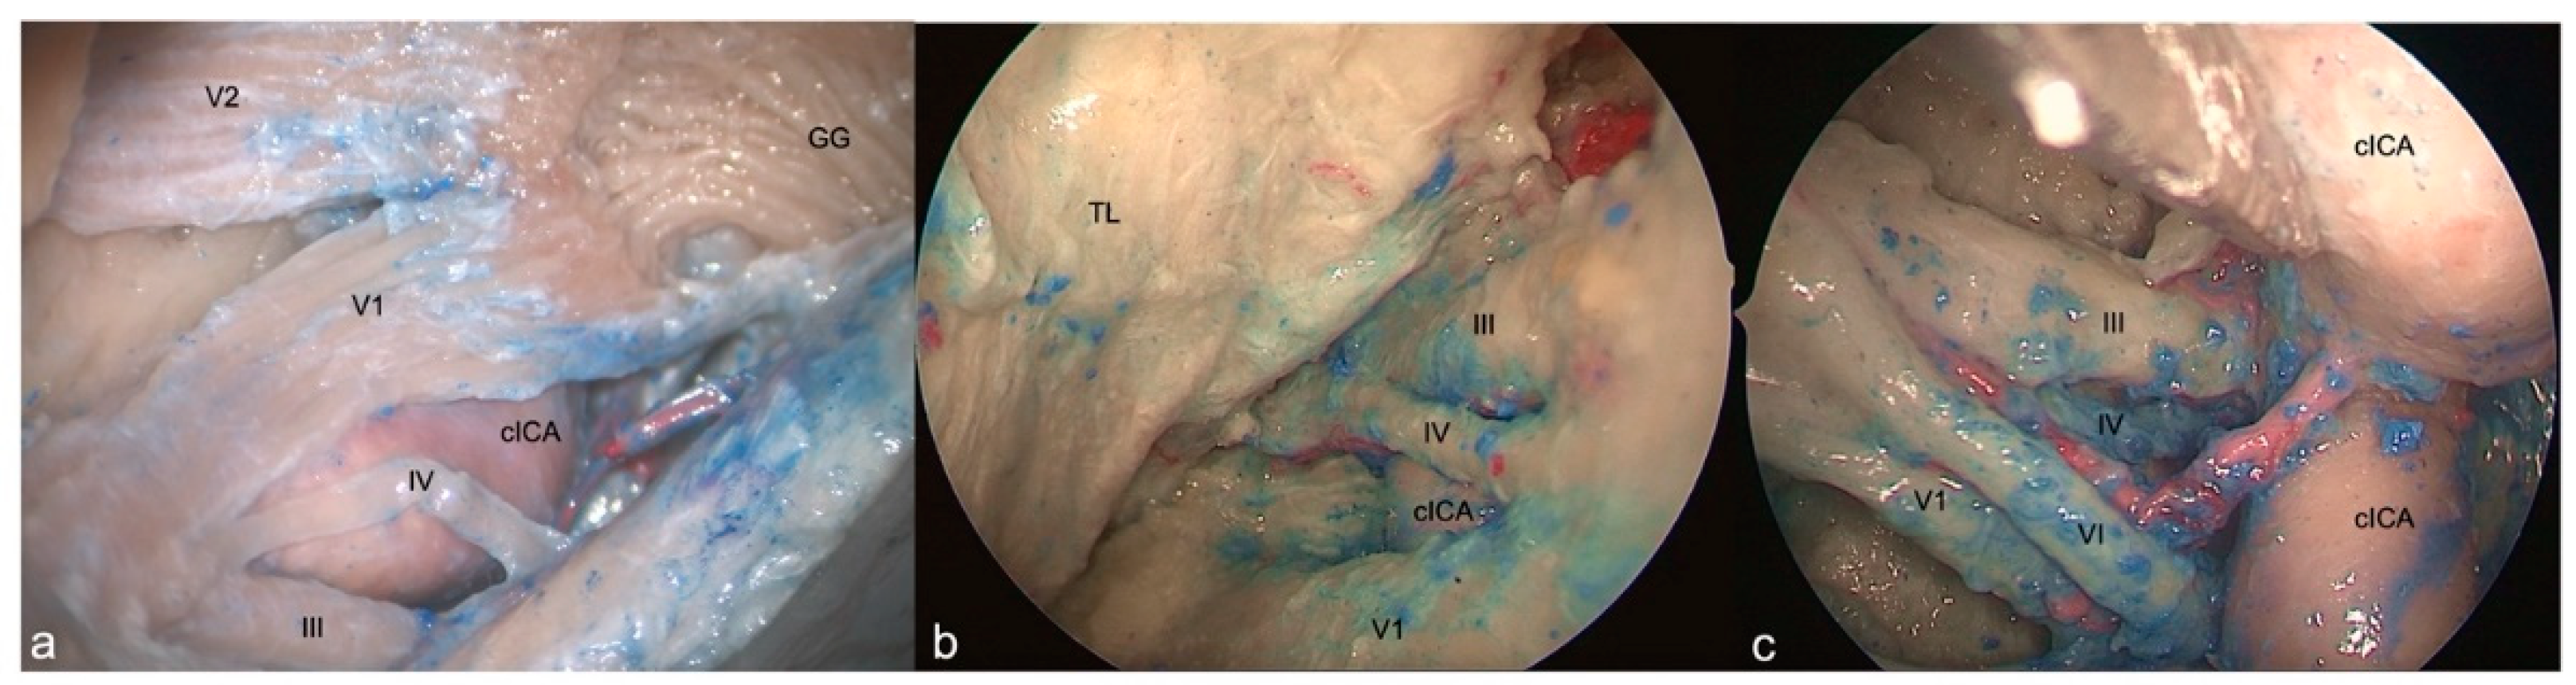

This area is bounded by the inferior border of the oculomotor nerve superiorly, the superior border of the trochlear nerve inferiorly and, by the segment of the dura of the roof of the cavernous sinus between the entry points of these two nerves. Its content is represented by the horizontal cavernous ICA (Figure 3a).

3.3.2. SETOA perspective

This triangle and its boundaries are completely exposed via the transorbital corridor just after interperiosteal-dural dissection of the lateral wall of the CS. It’s a very narrow space hiding medially the horizontal segment of the cavernous ICA (C4 segment [24]) (Figure 3b).

3.3.3. EEEA perspective

Just the apex of this triangle, where III and IV cranial nerves converge toward the SOF, can be exposed and it’s needed to displace the ICA medially and/or the cranial nerves laterally (Figure 3c).

3.4. Infratrochlear Triangle (Parkinson’s triangle)

3.4.1. FTOZ perspective

This triangle is delimited superiorly by the lower margin of the trochlear nerve, inferiorly by the upper margin of V1 and posteriorly by the line connecting the point where the trochlear nerve enters the roof of cavernous sinus and the point where the trigeminal nerve enters the Meckel’s cave. This region hosts the posterior bend of the cavernous ICA (C4 segment [24]) with its branches (meningohypophyseal trunk) (Figure 3a).

3.4.2. SETOA perspective

This region and its content are completely exposed via transorbital route; just after interperiosteal-dura dissection of the lateral wall of the CS, the antero-lateral aspect of the superior half of the ascending segment of the cavernous ICA is evident. Furthermore, after a gentle downward retraction of the proximal part of V1 is possible to identify the sixth cranial neve exiting from the Dorello’s canal under the Gruber’s ligament and coursing anteriorly in the lateral wall of the CS medially to V1. Displacing gently upward the trochlear nerve, it is possible to expose the meningohypophyseal trunk (MHT) arising from the posterior bend of cavernous ICA (C4 segment [24]) (Figure 3b).

3.4.3. EEEA perspective

Only the anterior narrow space of this triangle and its content, represented by the inferolateral trunk of the cavernous ICA (C4 segment [24]), are evident, because of the abducens nerve which covers the ophthalmic division of trigeminal nerve and of the horizontal tract of the cavernous ICA which obstacles the access to the posterior compartment (Figure 3c).

Figure 3. Right-side supra and infratrochlear triangles: FTOZ (a), SETOA (b), EEEA (c) perspectives. The boundaries of the supratrochlear are represented by the inferior border of the III c.n. superiorly, the superior border of the IV c.n. inferiorly and, by the segment of the dura of the roof of the cavernous sinus between the entry points of these two nerves; regarding the infratrochlear triangle, it is delimited superiorly by the lower margin of the trochlear nerve, inferiorly by the upper margin of V1 and posteriorly by the line connecting the point where the trochlear nerve enters the roof of cavernous sinus and the point where the trigeminal nerve enters the Meckel’s cave. (GG: Gasserian Ganglion; cICA: cavernous Internal Carotid Artery; TL: Temporal Lobe).